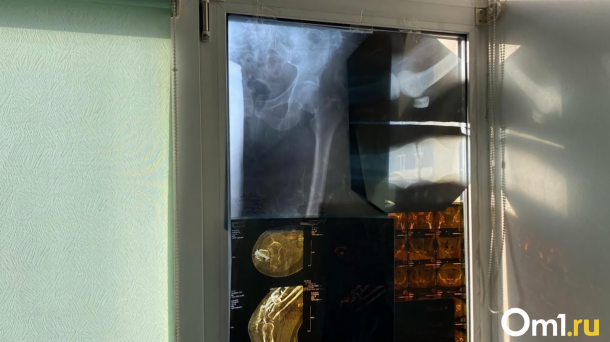

Глава региона заявил, что для жителей Тары и пациентов Тарской центральной районной больницы (ЦРБ) никаких изменений не предвидится. Министр здравоохранения Омской области Дмитрий Маркелов уточнил детали предстоящей реорганизации. Рентгенологическое отделение Тарской ЦРБ станет филиалом Клинического диагностического центра и продолжит обслуживать население северных районов области. Отделение не будет ликвидировано; обследования будут проводиться на прежнем месте и по-прежнему бесплатно, в рамках системы обязательного медицинского страхования (ОМС).

Дмитрий Маркелов подчеркнул, что реорганизация позволит увеличить количество проводимых исследований. Так, если раньше на двух аппаратах мультиспиральной компьютерной томографии (МСКТ) выполнялось не более 800 обследований в месяц, то теперь ожидается увеличение до 1 300. Кроме того, аппарат магнитно-резонансной томографии (МРТ), установленный в отделении в апреле, до сих пор не получил санитарно-эпидемиологическое заключение. Министр объяснил, что оборудование было приобретено в рамках национального проекта с целью превратить Тарскую ЦРБ в опорное медицинское учреждение для северных районов. Однако пока этого не произошло. Реорганизация поможет устранить существующие проблемы и улучшить качество медицинских услуг для населения севера области.